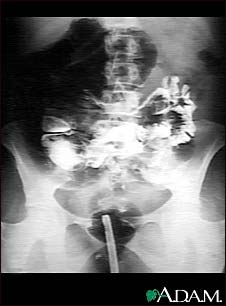

Volvulus - X-ray

A GI series in a patient with a twisted bowel (volvulus).